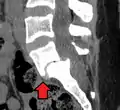

MRI of L5-S1 anterolisthesis